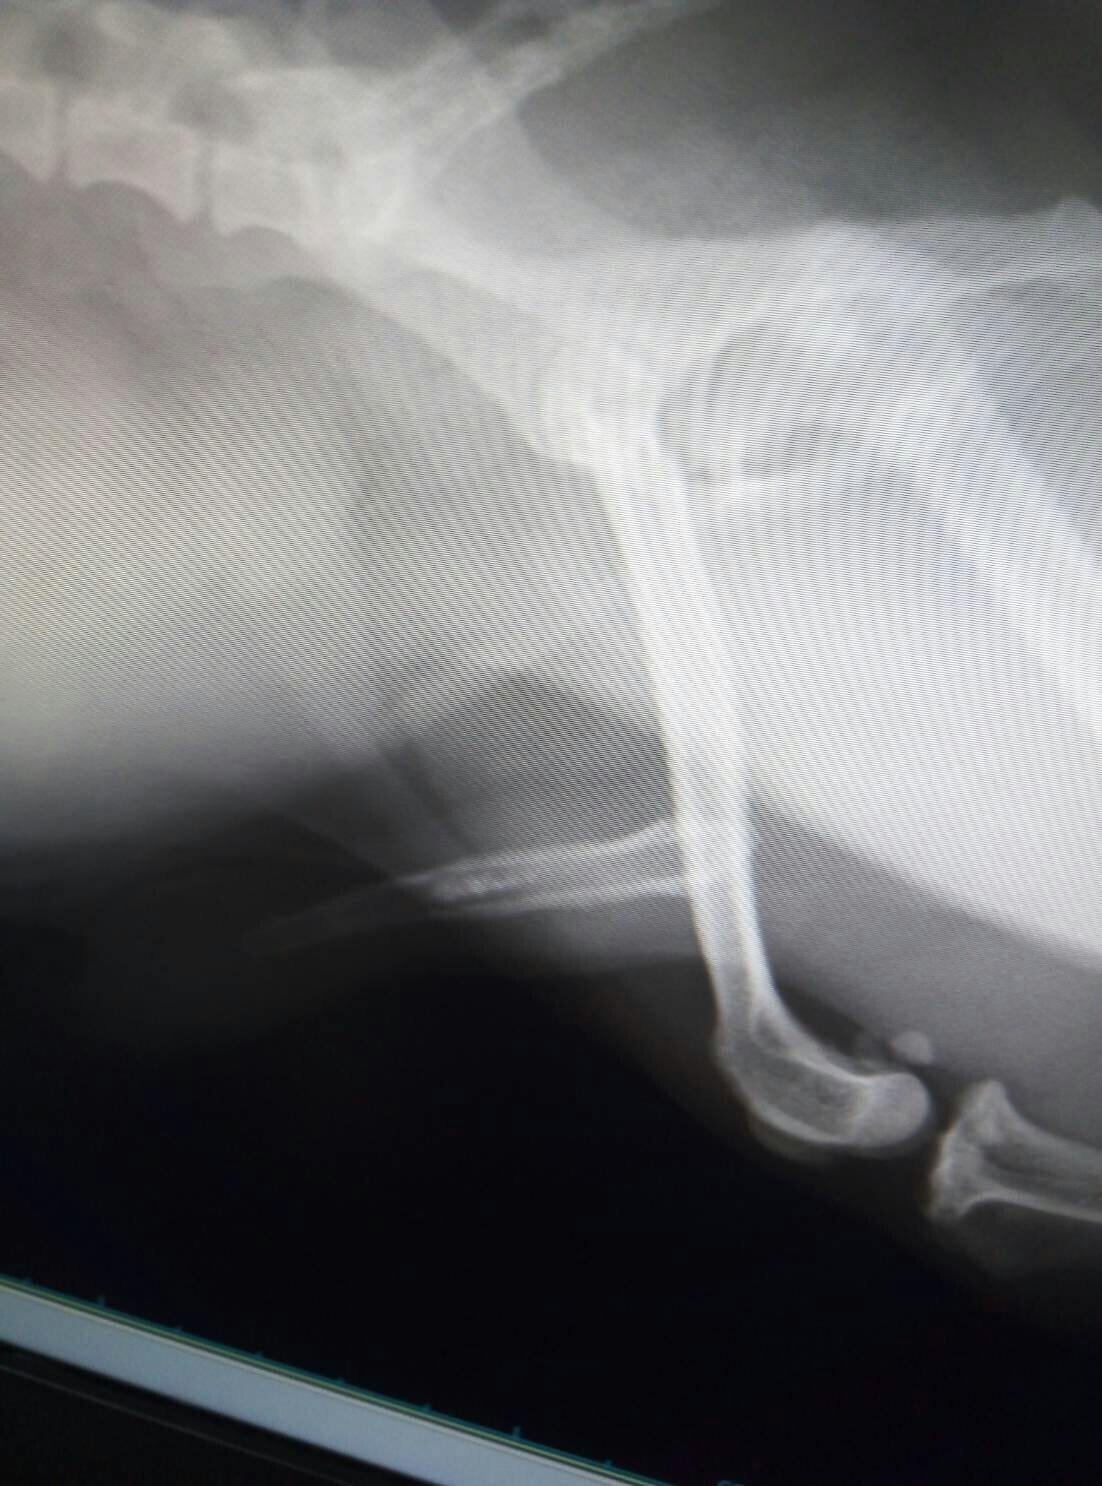

膀胱内での結石及び、尿道内で結石が詰まってしまっており、排尿障害がおきている。

さらに、前立腺肥大にともない膀胱から尿管を圧迫していることも判明。

かかりつけ医で、麻酔をかけて尿道カテーテルをその日に行い、結石を膀胱内に押し戻し応急処置をする処置を行うも、結石が大きいため、膀胱内へと押し戻しができず、さらに大きな動物病院(総合病院)を紹介され、すぐに行くように指示される。

再度、総合病院で検査を行い、麻酔をし尿道カテーテルで膀胱へと押し戻しができるかを試すことに。

それで、難しければ、尿道を切開し、石の摘出。その後、開腹し膀胱内内から石の摘出をするとの治療方針の説明をうける。

幸い、二度目のカテーテルで尿道から膀胱内に石を押し戻せることができ、尿道切開をする必要はなくなり、開腹をして膀胱内の石を取り除く治療がメインとなる。